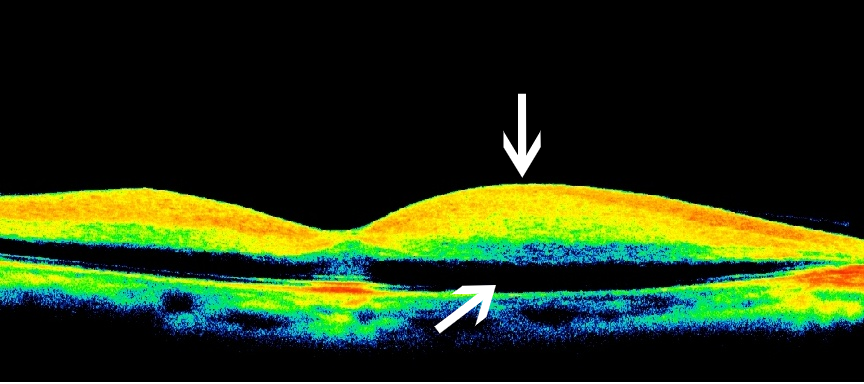

年龄相关性黄斑变性(湿性)

眼科ab超检查单怎么看常见眼底疾病检查结果的秒懂解读_https://www.jmylbn.com_新闻资讯_第25张

OCT:黄斑区神经上皮层轻度隆起,下方有黄色高反射的出血及新生血管,呈纺锤状

图片来源:天津市眼科医院